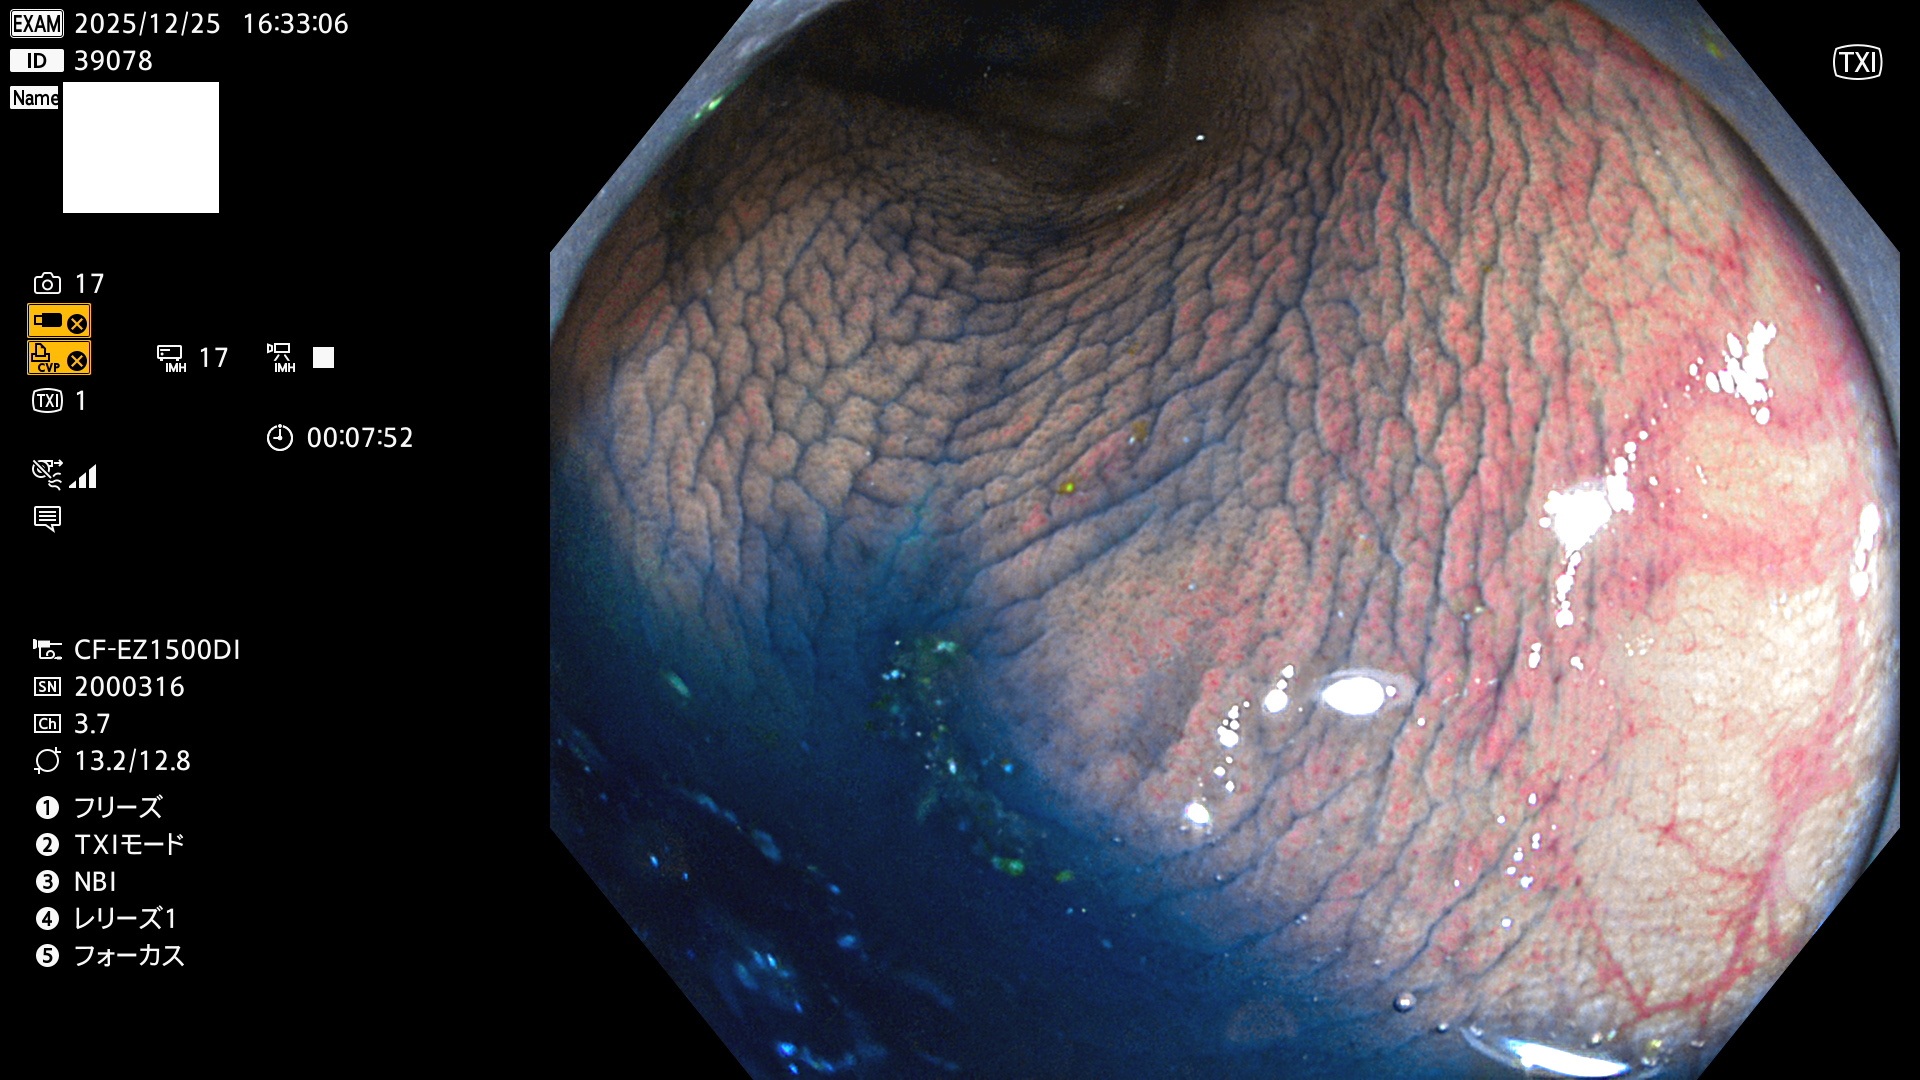

完全に平坦な物をUb、陥凹している物をUcと呼びます。Ubは認識が困難で、Ucはびらん(炎症)と紛らわしいために見落とされやすく、「内視鏡後・大腸癌」の原因になります。

毎週の検査(木・金・土・日)に発見されたUbとUc型・腺腫を、その週の日曜の夜にUPし1週間、提示します。

2025年12月18日〜12月29日の8日間(80件)13個 (Uc_ADR=13個/80人=16%)